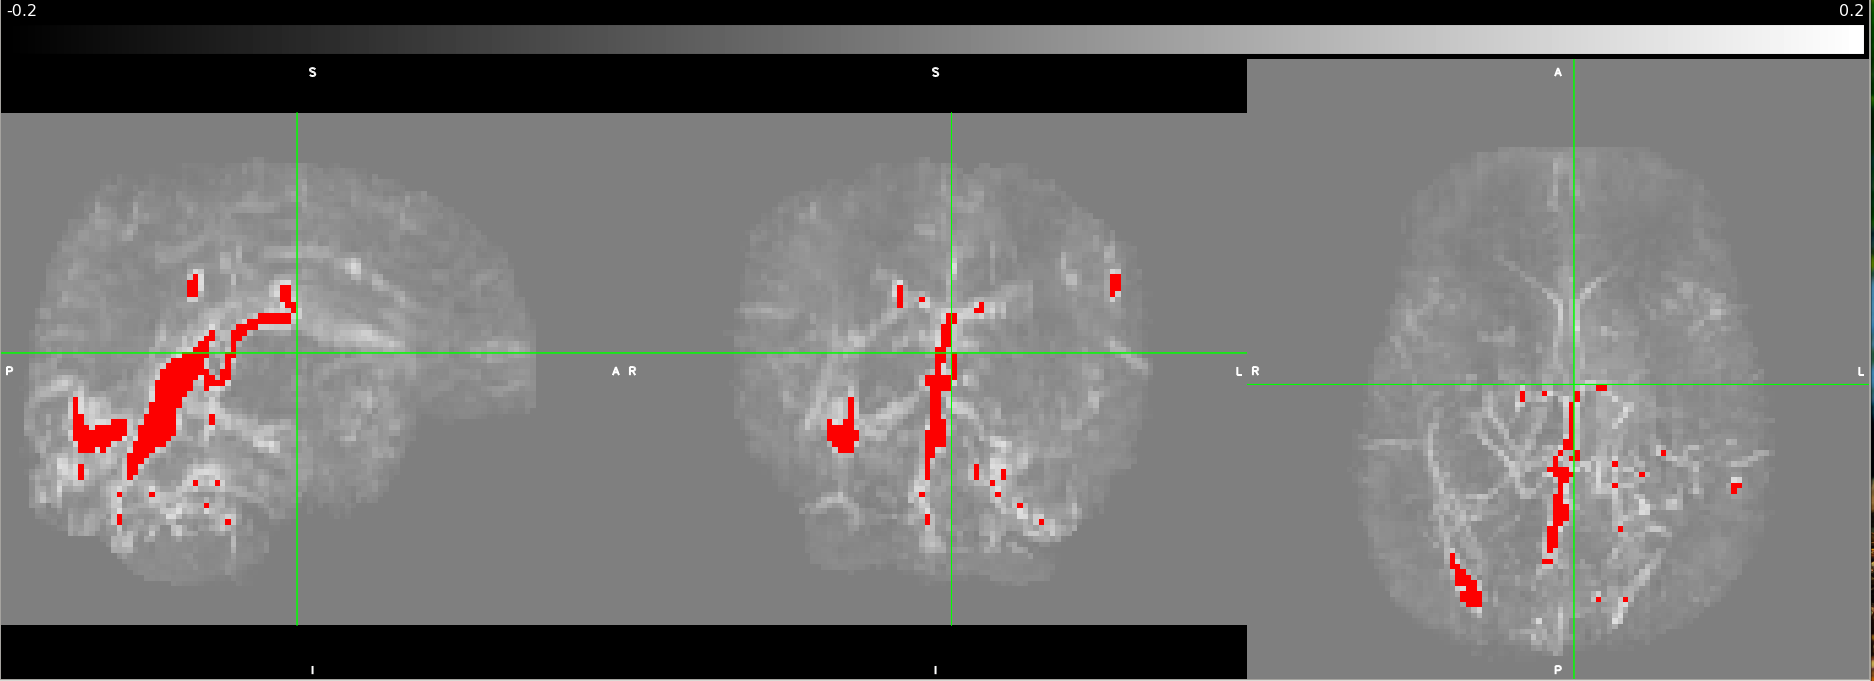

![]() |

|---|

| Fig 2: Processed QSM scan as underlay with a vessel mask projected in red at maximum intensity by thresholding the QSM image at 0.15ppm. The views from left to right are sagittal, coronal, and axial. |